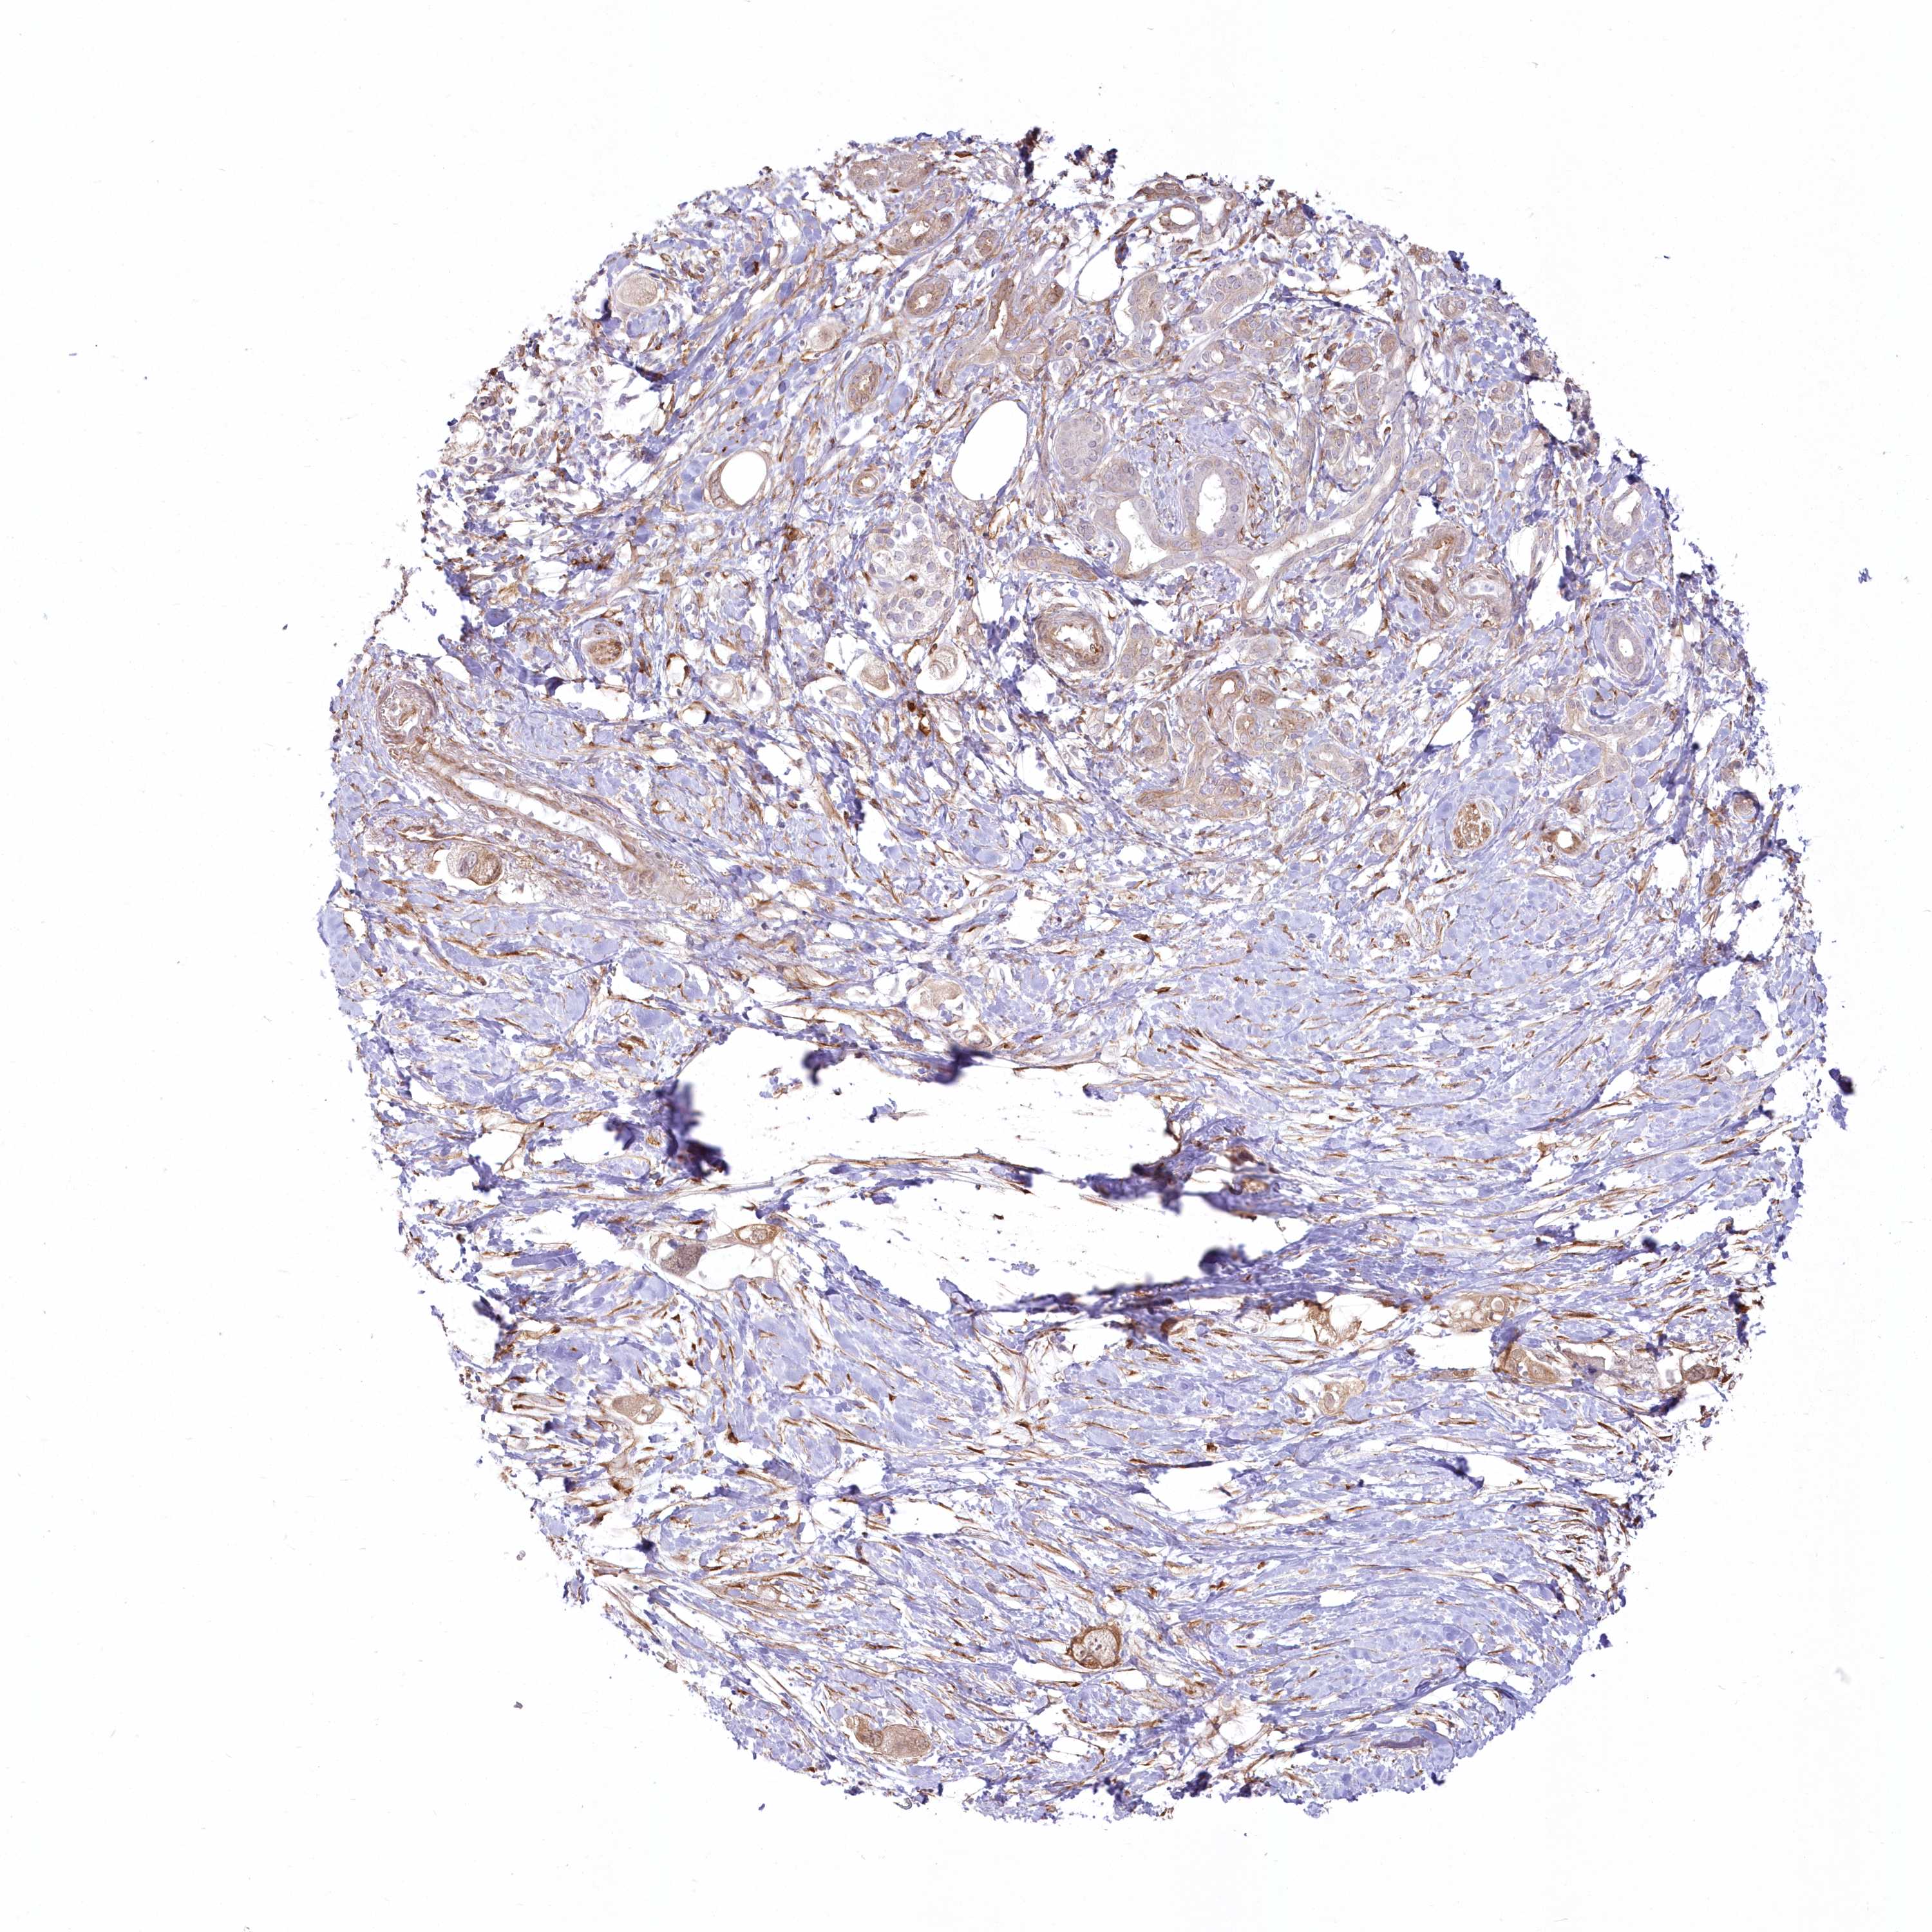

PANCREATIC CANCER - Protein expressioni

A mouse-over function shows sample information and annotation data. Click on an image to view it in a full screen mode. Samples can be filtered based on level of antibody staining by selecting one or several of the following categories: high, medium, low and not detected. The assay and annotation is described here.

Note that samples used for immunohistochemistry by the Human Protein Atlas do not correspond to samples in the TCGA dataset.

Antibody stainingi

Antibody staining in the annotated cell types in the current human tissue is reported as not detected, low, medium, or high, based on conventional immunohistochemistry profiling in selected tissues. This score is based on the combination of the staining intensity and fraction of stained cells.

Each image is clickable and will lead to virtual microscopy that enables deeper exploration of all samples and also displays staining intensity scores, fraction scores and subcellular localization as well as patient and tissue information for each sample.

Antibody HPA036471

Staining

High

Medium

Low

Not detected

Intensity

Strong

Moderate

Weak

Negative

Quantity

>75%

75%-25%

<25%

None

Location

Nuclear

Cytoplasmic/membranous

Cytoplasmic/membranous,nuclear

Adenocarcinoma, NOS